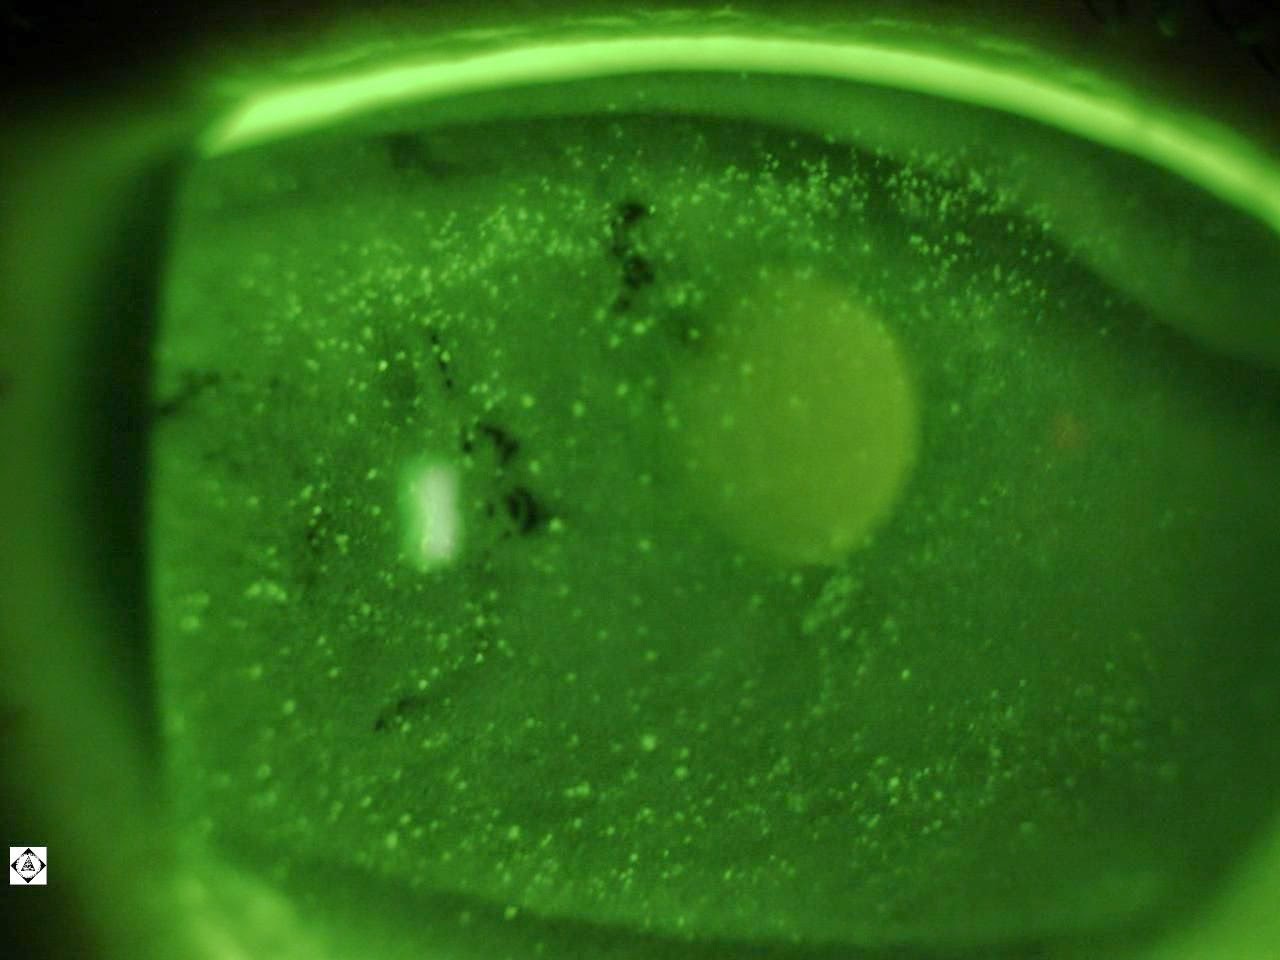

What Are Punctate Epithelial Erosions . They represent areas of epithelial cell loss and therefore stain positively with fluorescein. Pees are tiny, discrete spots of staining on the cornea's surface. Superficial punctate keratitis is a condition that affects the surface of the eye, specifically the cornea. Punctate epithelial erosions (pee) are evidence of ocular surface dryness. Pees can cause discomfort and irritation. The distribution of the pee can. It is a characterized by a breakdown or damage of the epithelium of the cornea in a pinpoint pattern, which can be seen with examination with a slit. Punctate epithelial erosions (pees) are a feature of many ocular surface diseases and present as dots on the corneal epithelium. Tear film instability, desiccation, or inflammatory changes of the cornea resulting in a breakdown of the healthy.